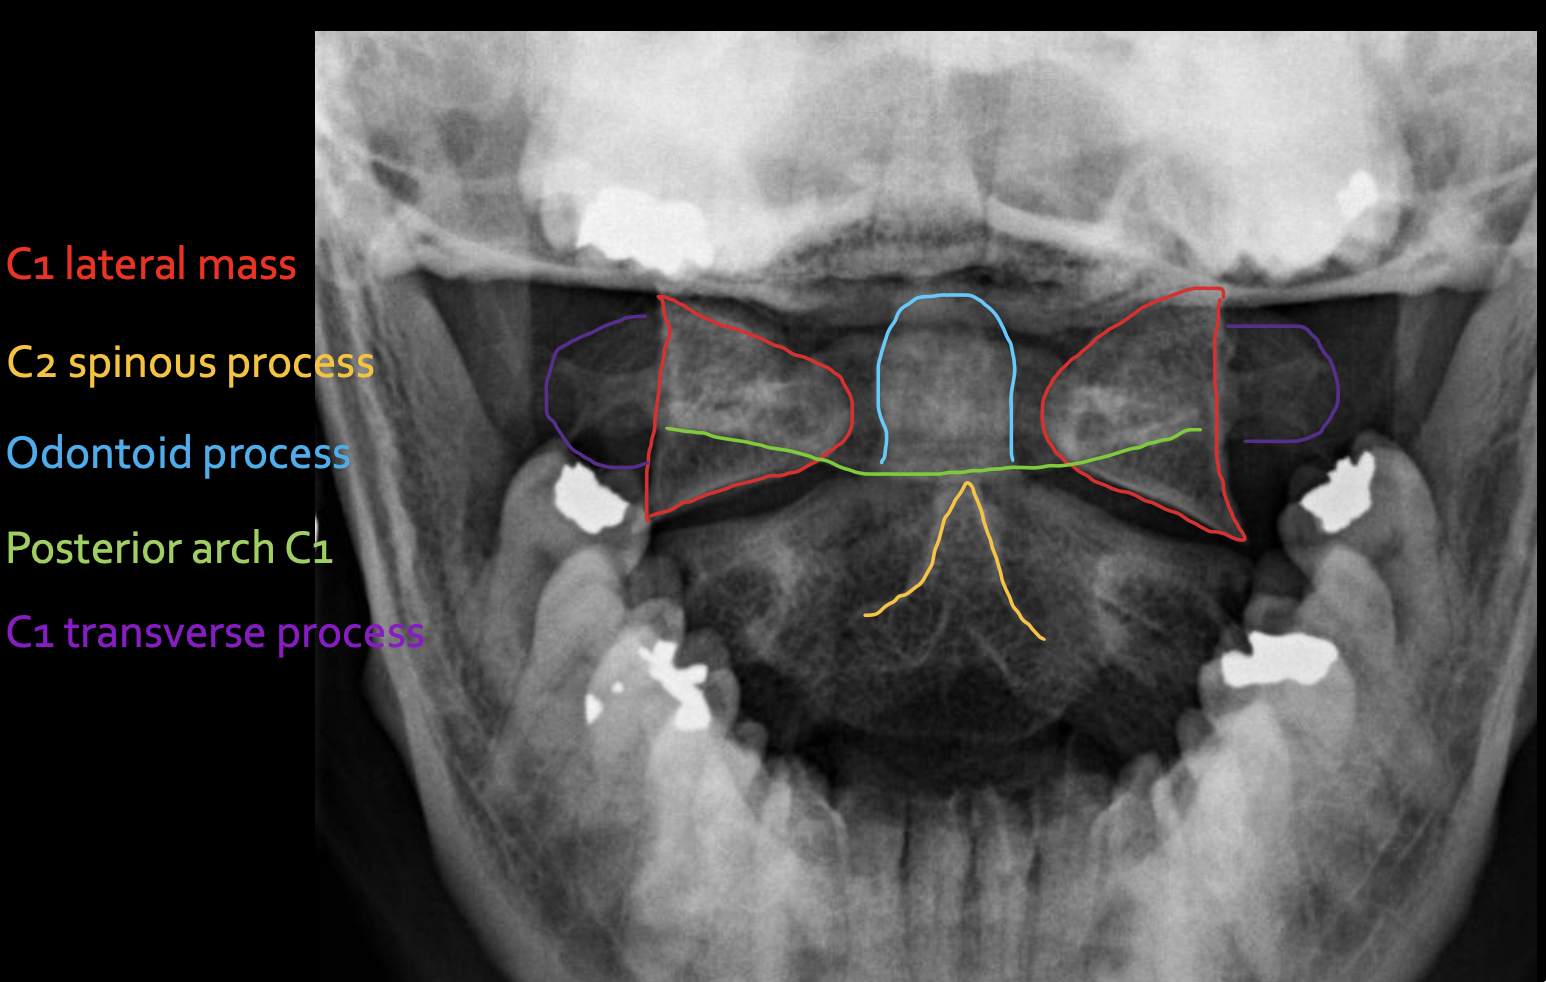

寰椎侧块

C1 lateral mass

枢椎棘突

C2 spinous process

寰椎后弓

Posterior arch C1

寰椎横突

C1 transverse process